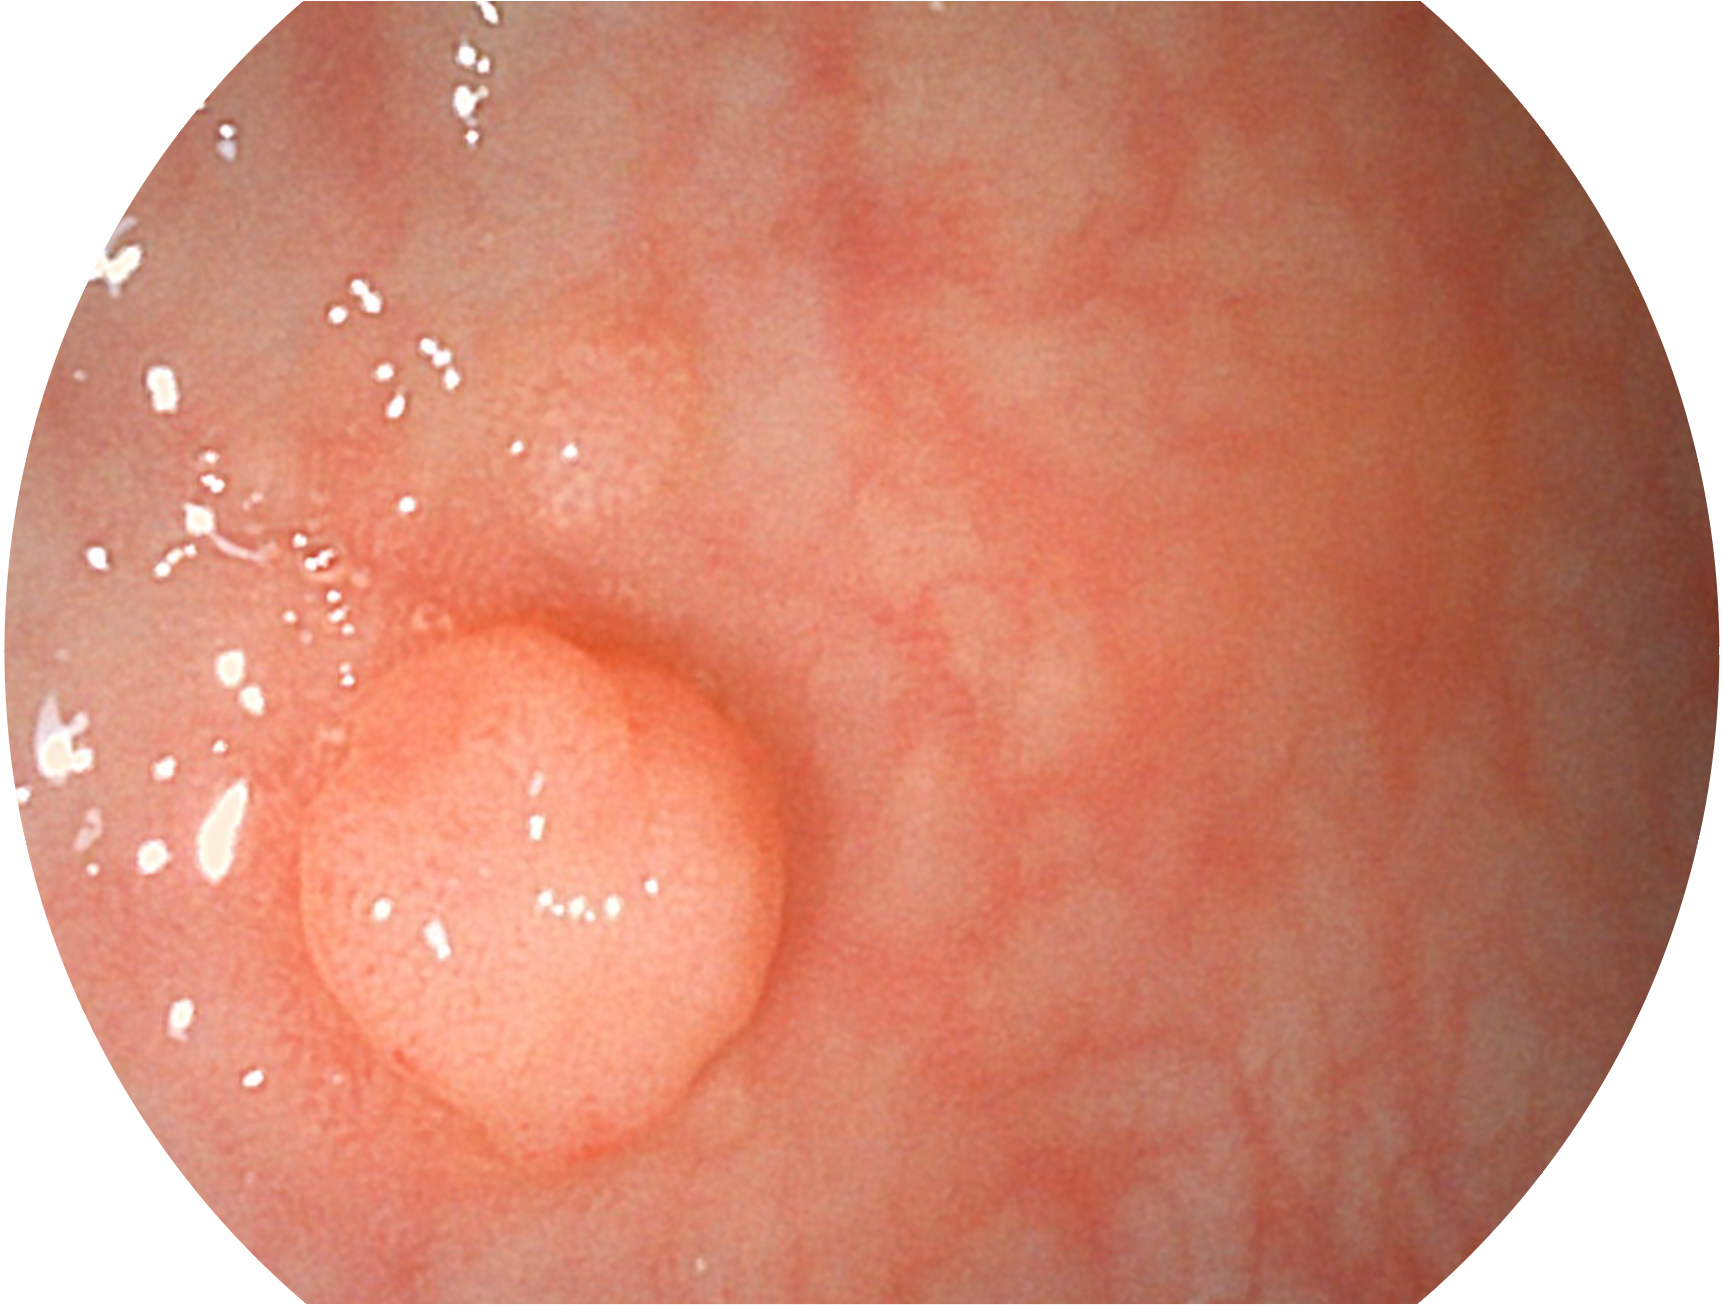

開(kāi)立新開(kāi)發(fā)的內(nèi)鏡染色技術(shù),主要是基于多波長(zhǎng)LED 光源的開(kāi)發(fā),VLS-55Q 四波長(zhǎng)LED 光源是由四個(gè)不同顏色的LED光按照相應(yīng)照明模式所規(guī)定的特定發(fā)光比例進(jìn)行合束后形成,合束后形成的照明光的光譜由紅光、綠光、藍(lán)光及藍(lán)紫光這四個(gè)不同的波段范圍構(gòu)成。具有更高光譜自由度,通過(guò)光譜比例的控制,實(shí)現(xiàn)了聚譜成像技術(shù),英文全稱為“Spectral Focused Imaging, SFI”,縮寫為“SFI”和光電復(fù)合染色成像技術(shù),英文全稱為“Versatile Intelligent Staining Technology, VIST”,縮寫為“VIST”。